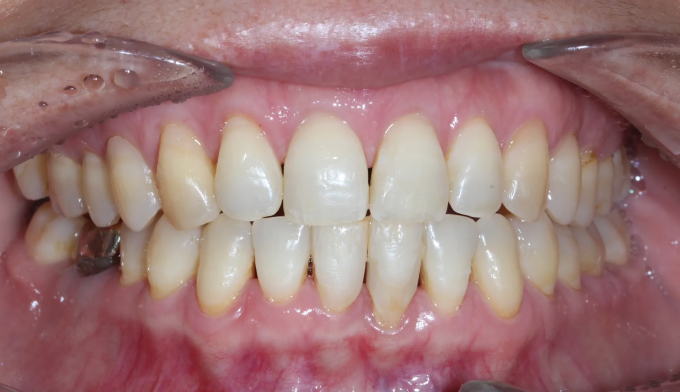

기존에 아래 앞니 사이 공간들에 레진이라는 치아색 나는 재료로 메워놓으셨던 분입니다. 나이가 들면서 잇몸이 약해지게되고 앞니가 점점 더 벌어질 수 있습니다.

타치과에서 다시 레진으로 공간을 없애려고 하였으나 더이상의 보철치료를 원하지 않으셔서, 기존에 존재하던 레진을 제거하면서 동시에 앞니 사이 공간을 교정치료를 이용해 닫아주기로 하였습니다.

기존에 앞니가 벌어지게 된 이유인 치주염을 치료하면서 동시에 앞니 공간을 교정을 통해 닫아줍니다.

총 교정기간은 9개월입니다.